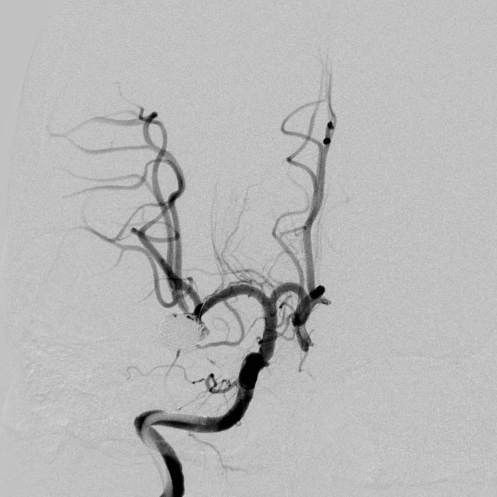

病史:中年女性,新冠感染,颅内动脉瘤破裂,Hunt-Hess 4级

最终,动脉瘤瘤体致密栓塞,各个分支保留良好